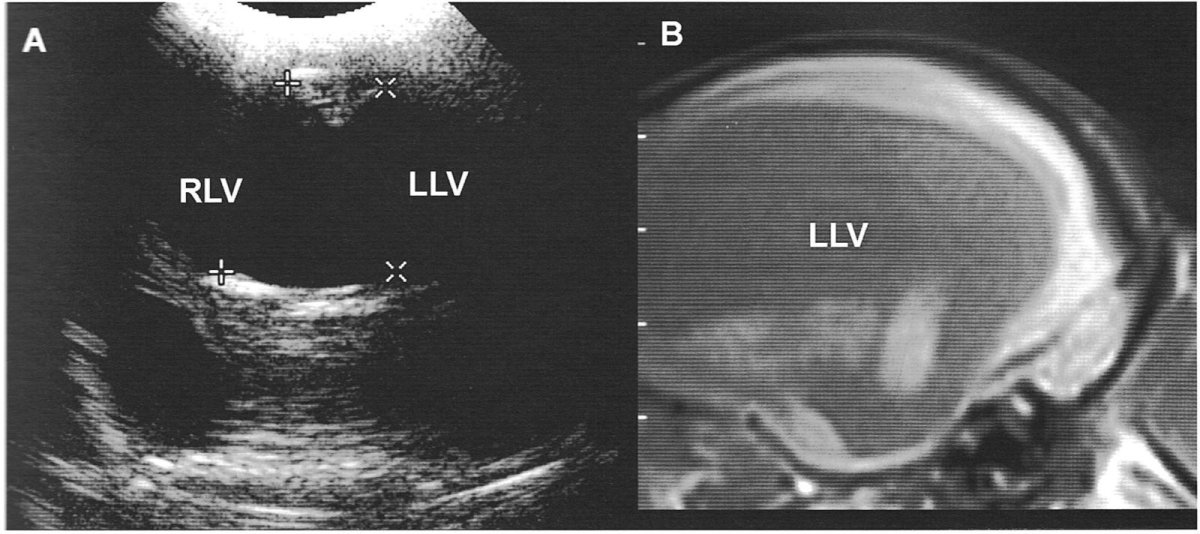

Абдоминальный парацентез